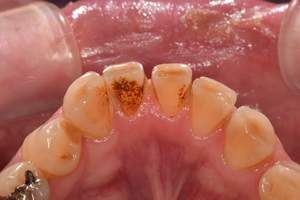

歯石除去

治療前

治療後

| 年齢 | 25歳・男性 |

| 主訴 | 歯石をとりたい・検診 |

| 治療内容 | 各種検査・歯石除去 |

| 治療期間 | 60分 |

| 費用 | 初診料3,000〜4,000円前後 +歯石除去約1,000円 |

| リスク・副作用 | ・処置後に歯がしみることがあります。 ・歯と歯の間に隙間ができるので、息が漏れ発音しにくいと感じることがあります。 ・歯ぐきの炎症が軽減すると歯ぐきが引き締まり、歯が長く見えることがあります。 |

| 担当者所見 | 前歯の裏側にすぐに歯石が溜まってしまいザラザラして気になるとご相談いただいたので適切な歯ブラシの当て方とフロスの通し方をお伝えさせて頂きました。 |